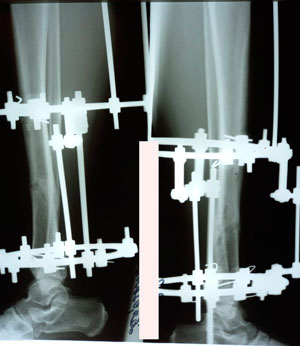

Исходник - 21 год.

Дата операции - 22.09.2020

на фиксации